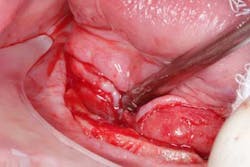

Surgery commenced. Implants on the lower arch were placed first (figures 7 and 8) and then we switched to the maxillary. The teeth were removed (figures 9 and 10) and the ridge was evened out (figures 11-13). The implants were aligned with the denture (figure 14) and then placed accordingly (figures 15-17). Healing caps were put on, and we were ready to start the restorative phase (figures 18-19).